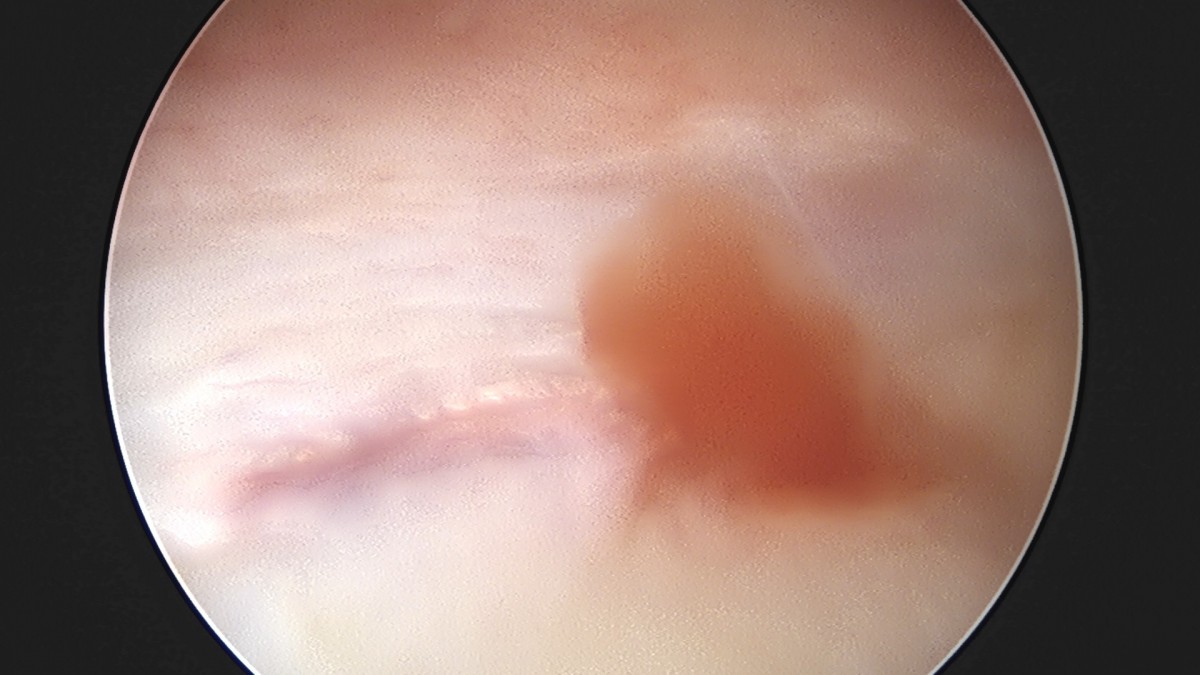

이재상원장님 어깨 견봉하 감압술 및 관절낭 이완술 음성O 환자